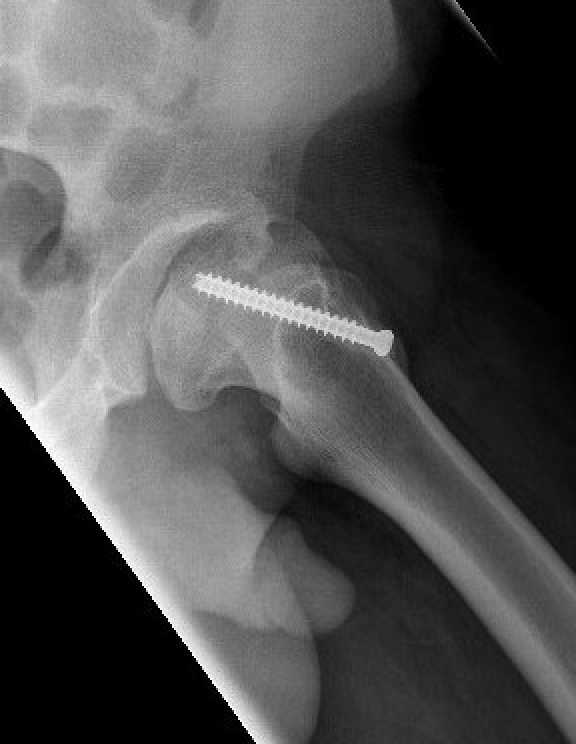

Intertrochanteric / Southwick

Technique

Removal anterolateral bone wedge below lesser trochanter

Valgising / flexion / internal rotation

Base of neck / Kramer

Closing wedge anterior and superior